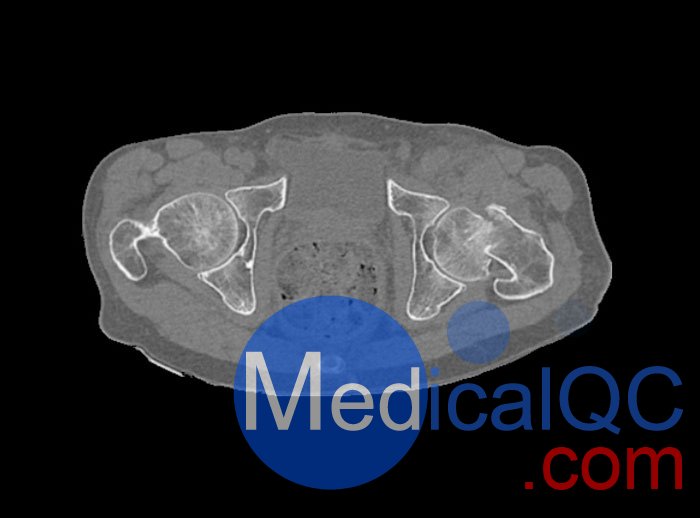

WEK54-01股骨頸骨折骨盆模型,WEK54-01骨盆模體詳細介紹:

WEK54-01股骨頸骨折骨盆模型,WEK54-01骨盆模體模擬沒有靜脈造影劑的骨盆(天然)。它覆蓋了整個骨盆,直到第五腰椎。

左側股骨頸移位骨折。

該模型可用于 CT(包括 CBCT)和射線照相,以評估和優(yōu)化成像性能和后處理應用,包括支持 AI 的應用。它也適用于培訓目的。

WEK54-01股骨頸骨折骨盆模型,WEK54-01骨盆模體提供了對軟組織和骨組織的詳細而逼真的模擬。空隙中填充著約-160HU的纖維素-聚合物復合材料。

WEK54-01股骨頸骨折骨盆模型,WEK54-01骨盆模體成像效果圖: